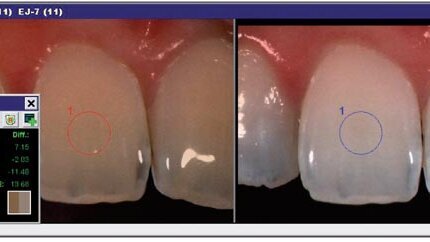

A comprehensive examination and smile analysis using a spectrophotometer (Spectroshade, MHT) revealed healthy dentition with a shade range between D4 and A4 (Fig. 1).

Fig. 1: Smile analysis before whitening.

A smile analysis after treatment revealed the efficacy of tooth whitening and confirmed that the treatment had been completed successfully (Fig. 6).

Fig. 6: Smile analysis after whitening.

Shade changes can be measured as shade guide units on a value-oriented, classic vita shade guide or as ΔE values defined by the Commission Internationale de l’Éclairage (CIE) L*a*b* colour system. ΔE is the shortest distance in the CIE L*a*b* colour space between the colours being compared and is determined using the equation ΔE= (ΔL*2 + Δa*2 + Δb*2)1/2 where L* represents lightness, a* corresponds to the red–green axis (positive value indicates red, negative indicates green), and b* corresponds to the yellow–blue axis (positive value indicates yellow, negative value indicates blue). The shade change as indicated by ΔE was obtained by overlapping the image of the same tooth before and after tooth whitening (Fig. 7), using the Spectroshade analysis software (Version 2.41).

An increase in ΔE after tooth whitening is usually attributed to an increase in L* values and a decrease in b* values. It is interesting to note that ΔE values varied according to the teeth although all teeth were treated with the same concentration and same exposure time. This suggests that each tooth has its own degree of whitening, which is a very important factor that influences the efficacy of tooth whitening.